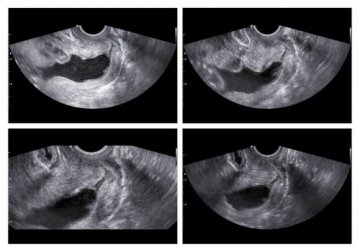

Comment l’insuffisance cervicale est-elle diagnostiquée ?

Si vous êtes concernée par l’un des procédés précédents, vous pouvez vous soumettre à une échographie de diagnostic. Vous pouvez également faire un examen du pelvis ou bien un examen d’ultrason, afin de mesurer la longueur du col de l’utérus ainsi que son ouverture.